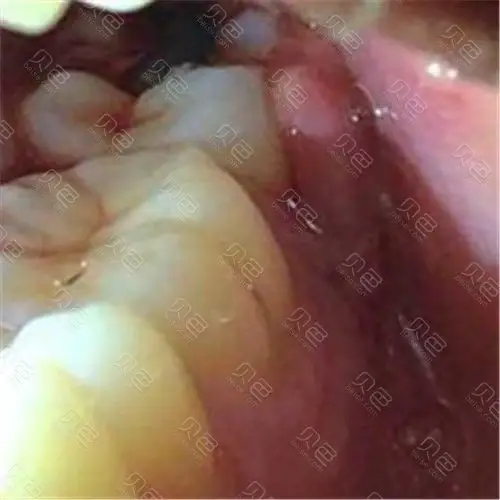

牙槽里边的软肉肿痛